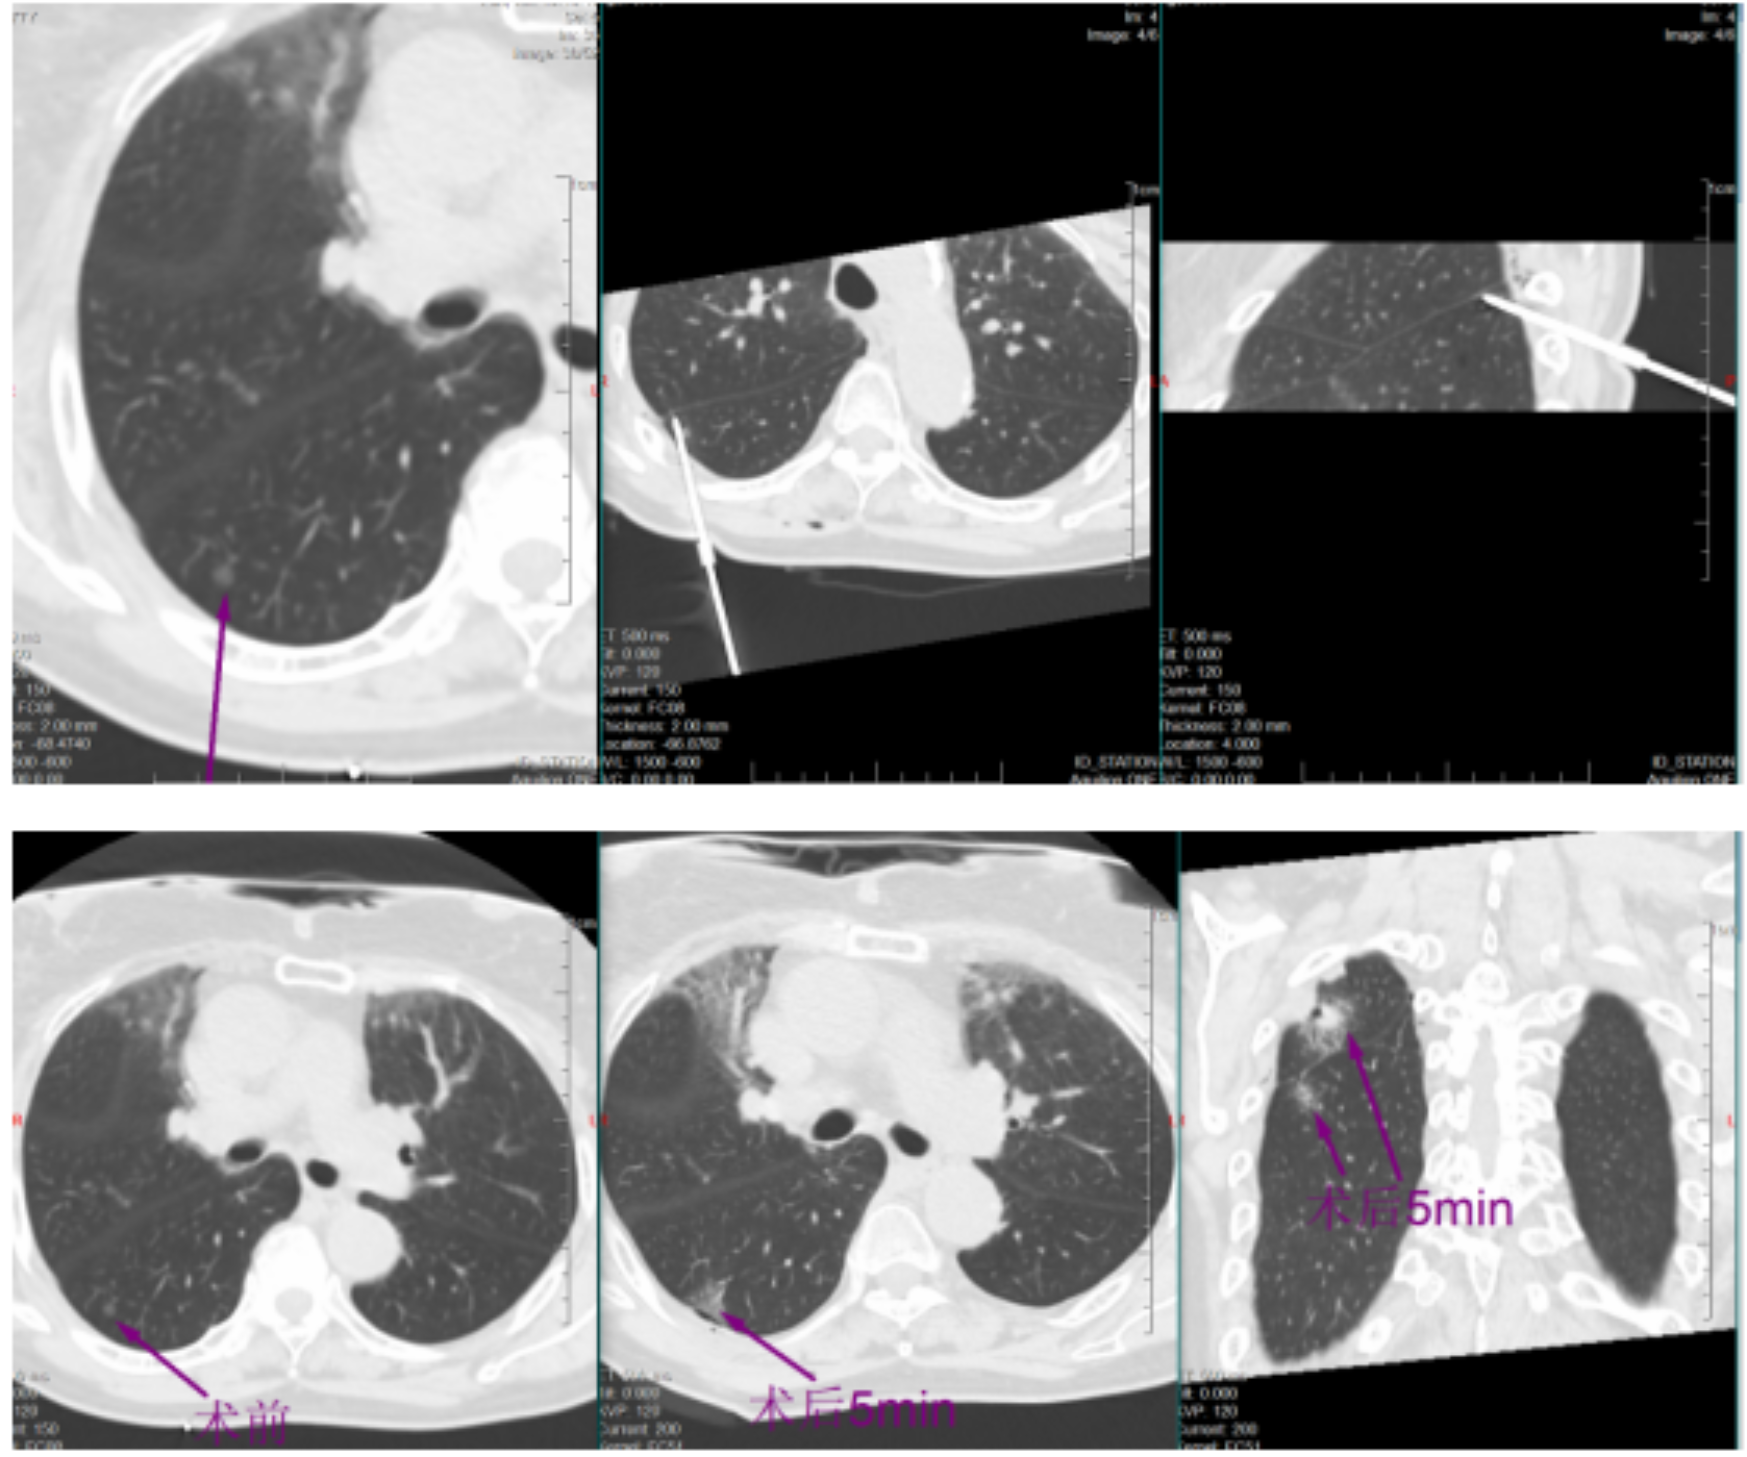

挑战随即开始。帕金森病导致黄女士身体不时微颤,这对需要毫米级稳定的穿刺是巨大干扰。于明川凝神屏息,双手稳如磐石,细微调整针道,在CT的实时引导下,消融针稳稳穿过8毫米的磨玻璃结节,精准停在胸膜前方3厘米处,完美避开胸膜危险区。“开始消融,30瓦一分钟!”随着指令下达,微波消融针开始加热,热量在结节处缓缓扩散,将病灶逐步凝固坏死。黄女士全程清醒,未感丝毫不适。

一分钟后,复查CT显示,结节被一圈磨玻璃密度影完整包裹,这意味着病灶已完全处于烧灼区内,第一枚结节消融成功!

稍后,于明川与冯文汉等团队成员密切配合,向难度更高的第二枚结节发起冲击。这枚结节藏在叶间裂与胸膜构成的狭小夹角内,可操作空间极小,如同在“夹缝中绣花”。按照术前预案,于明川放弃平行进针思路,采用由下而上的特殊进针方式,巧妙避开关键解剖结构。针尖精准抵达结节区域,经过反复测量确认安全后,30瓦功率持续消融一分钟。术中,黄女士的心率、血压始终平稳,未出现任何不良反应。术后CT扫描证实,结节被完全覆盖,烧灼区与叶间裂仅隔几毫米,这毫厘之间的精准,正是生命安全的坚实屏障。

一小时后,铅门再次打开。于明川将黄女士的儿女引至屏幕前,影像清晰地显示:两枚结节已被完全覆盖,消融范围边缘距离关键解剖结构仅有毫厘之差。“两个结节都顺利消融成功了,没有并发症,手术很成功!” 话音落下,黄女士儿女心中悬了许久的大石终于落地。看着术后安然躺在病床上、面容平和的母亲,他们眼中盈满欣慰。